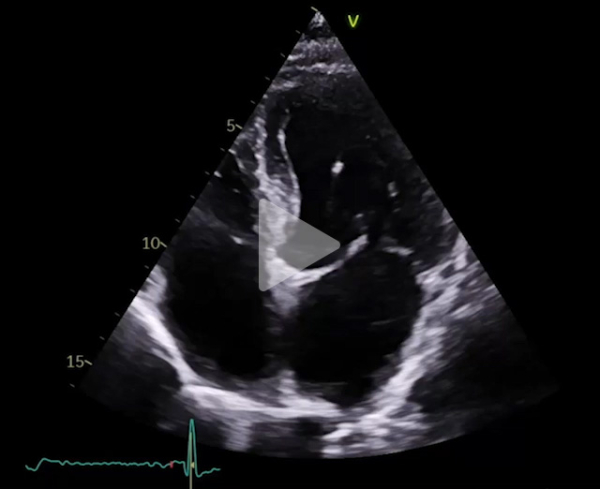

Figure 1

ETT au repos

Vidéo 1